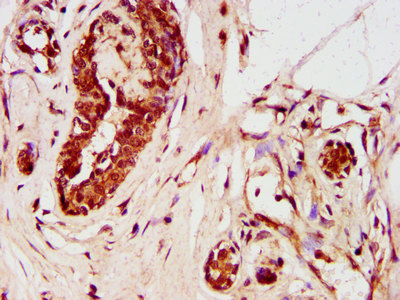

IHC image of CSB-PA026966LA01HU diluted at 1:400 and staining in paraffin-embedded human breast cancer performed on a Leica BondTM system. After dewaxing and hydration, antigen retrieval was mediated by high pressure in a citrate buffer (pH 6.0). Section was blocked with 10% normal goat serum 30min at RT. Then primary antibody (1% BSA) was incubated at 4°C overnight. The primary is detected by a biotinylated secondary antibody and visualized using an HRP conjugated SP system.